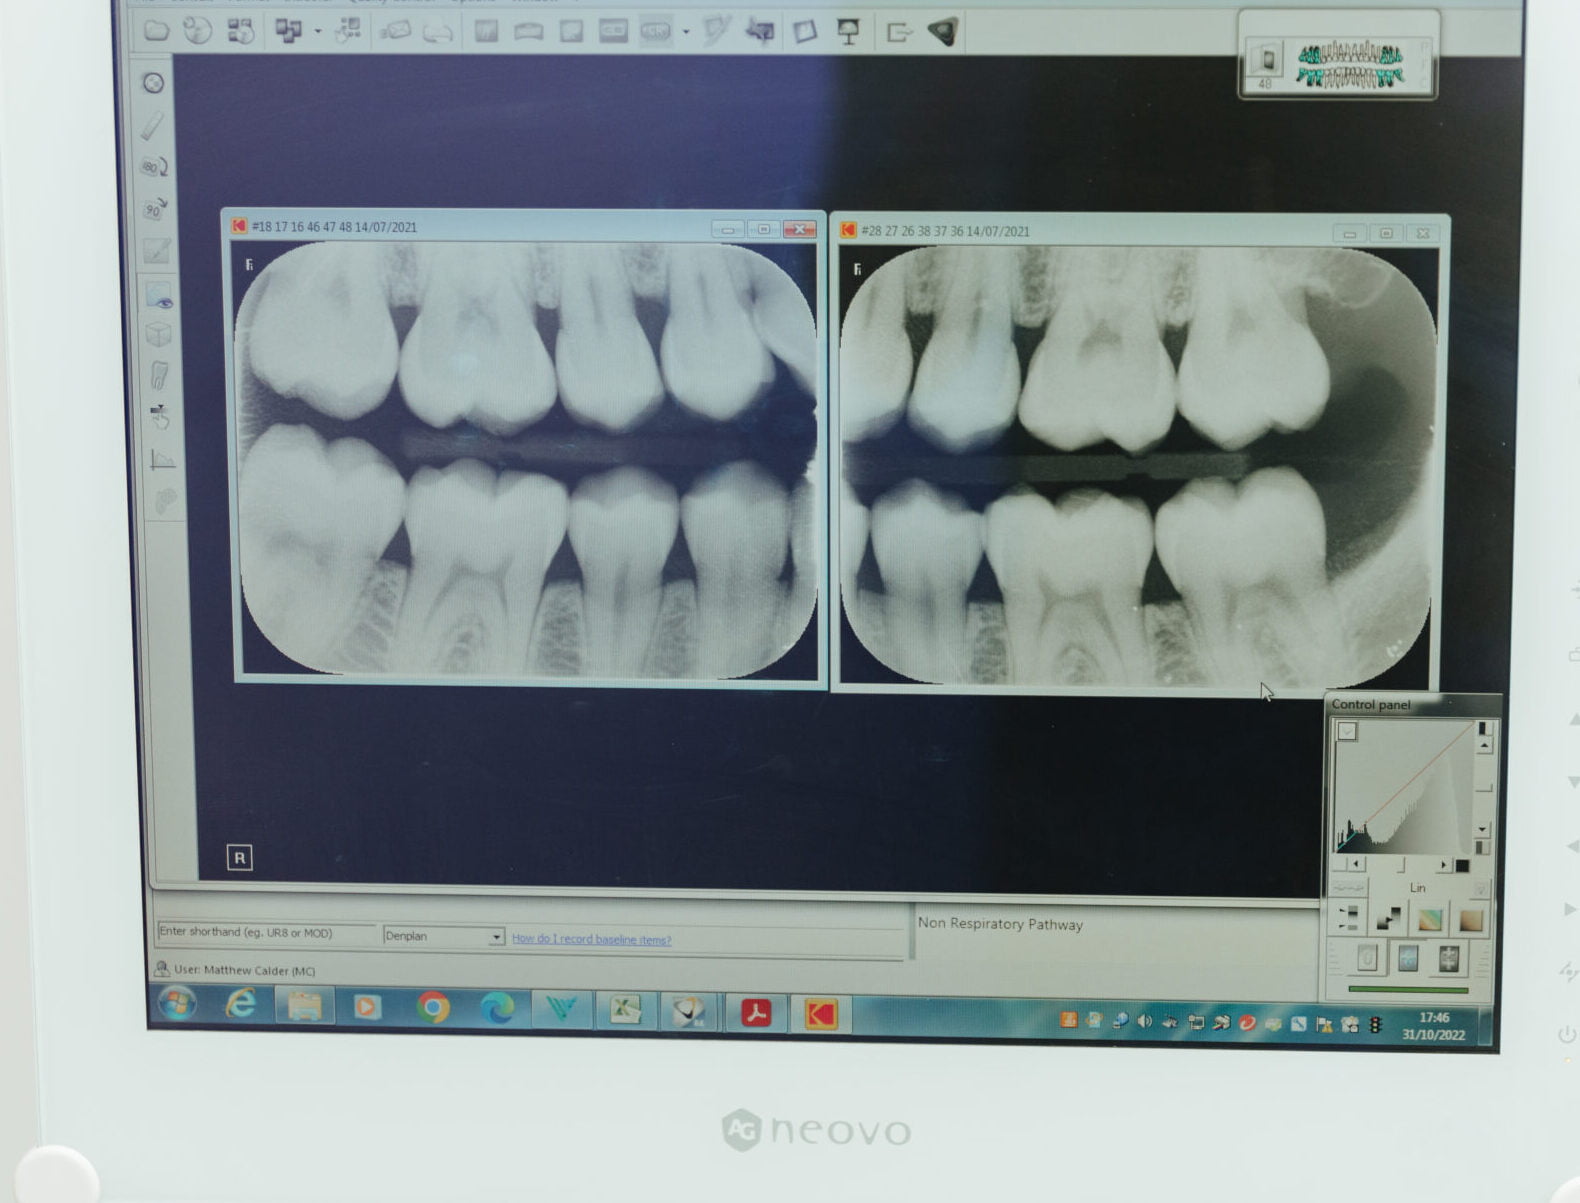

Further investigations like dental x-rays may also be required. At Cwmbran Dental Care, we use digital x-rays, which mean lower radiation dosage for you and results which come back almost immediately.